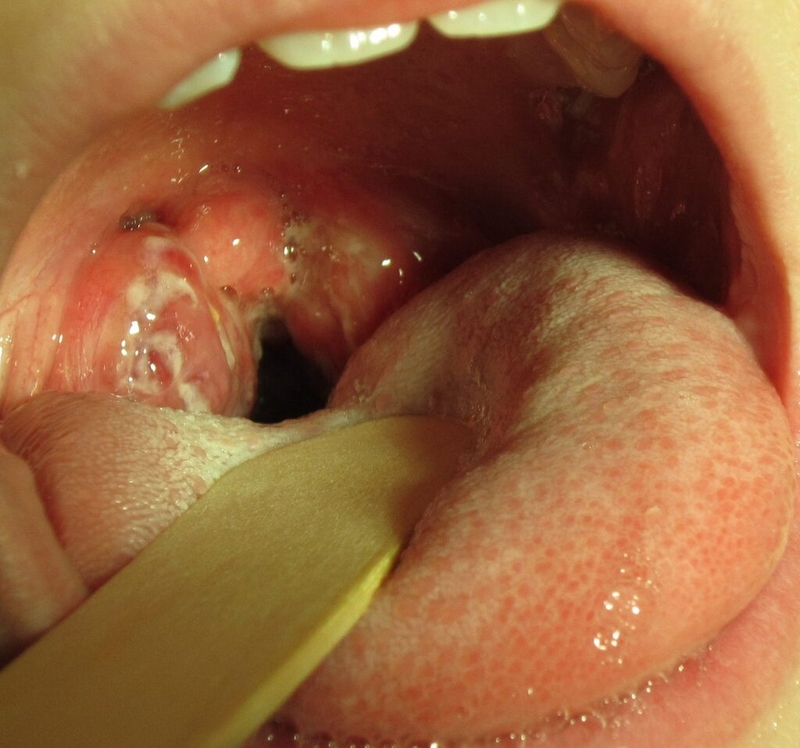

Trong khi đó, ở nam giới, bệnh biểu hiện qua tình trạng tiết dịch từ dương vật, có thể là dịch trắng, vàng hoặc xanh. Họ cũng có thể cảm thấy đau rát khi đi tiểu hoặc đau và sưng ở tinh hoàn, mặc dù triệu chứng này ít gặp hơn. Các hình ảnh bệnh Chlamydia trên lâm sàng thường cho thấy niêm mạc vùng sinh dục viêm đỏ, sưng tấy hoặc tiết dịch mủ, giúp bác sĩ dễ dàng nhận biết và chẩn đoán tình trạng nhiễm khuẩn.

Với những hậu quả nghiêm trọng mà Chlamydia có thể gây ra, việc thăm khám và điều trị kịp thời khi phát hiện bất kỳ dấu hiệu bất thường nào ở cơ quan sinh dục là điều cần thiết. Điều này không chỉ giúp bảo vệ sức khỏe cá nhân mà còn ngăn ngừa các biến chứng lâu dài. Dưới đây là một số hình ảnh bệnh Chlamydia để phần nào giúp bạn nhận diện được dấu hiệu sớm của bệnh.